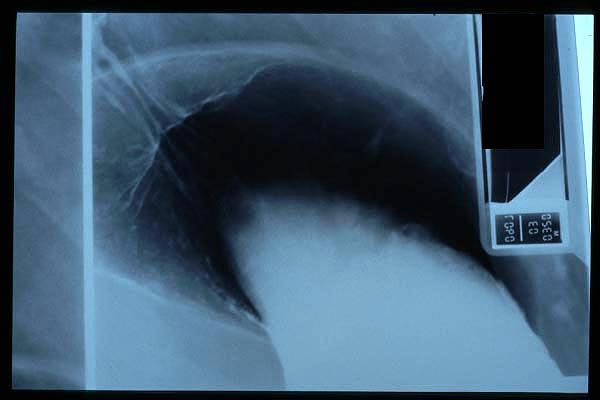

MO Distres respiratorio del adulto por trauma.